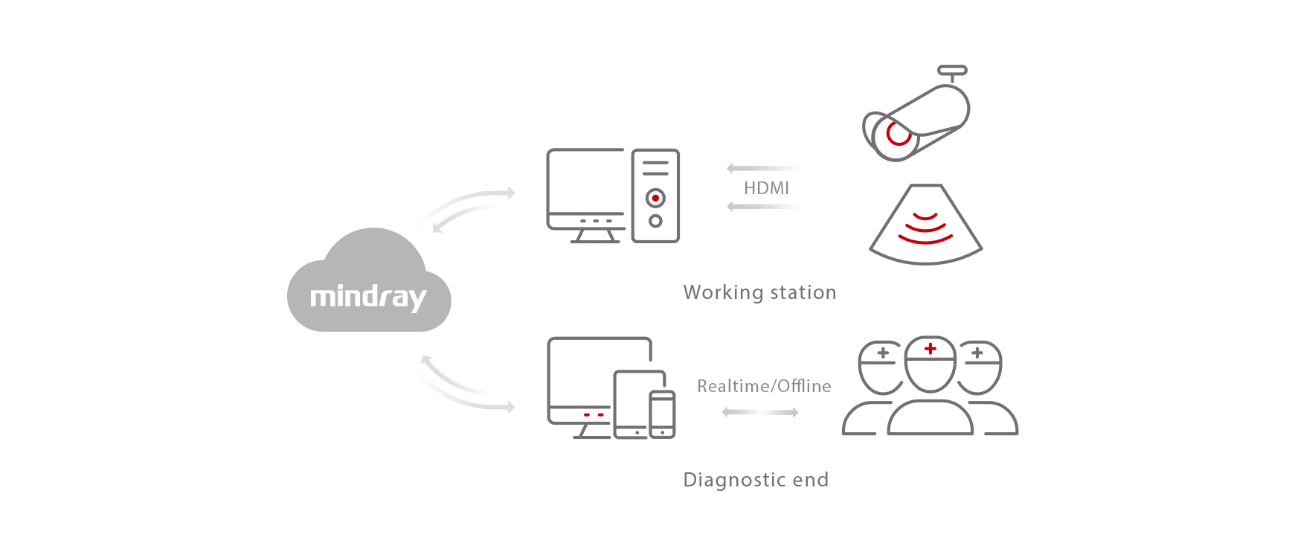

- 2. Remote consultation, training, and teaching